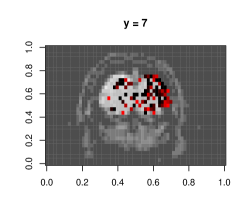

This dataset is due to Wakeman & Henson (2015), where each of the 19 subjects go through 9 runs of consecutive visual tasks. Blood oxygen level readings are recorded across time as 3D images made of (total 135,168) voxels. Here we use the data from a single run and task on subject 1, and aim to estimate dependence patterns of readings across 210 time points and areas of the brain.

We fit separate regressions at each voxel (Appendixย E), with second order autoregressive terms, neighboring voxel readings and one-hot encoded visual task categories in the design matrix. After applying the e-value feature selection, we compute the F-statistic at each voxel using selected coefficients only, and obtain their p-values. Fig.ย 7.1c highlights voxels with p-values . Left and right visual cortex areas show high spatial dependence, with more dependence on the left side. Signals from the right visual field obtained by both eyes are processed by the left visual cortex. The lop-sided dependence pattern suggests that visual signals from the right side led to a higher degree of processing in our subjectโs brain. We also see activity in the cerebellum, the role of which in visual perception is well-known (Calhoun etย al., 2010; Kirschen etย al., 2010).

Appendix E Details of fMRI data implementation

Typically, the brain is divided by a grid into three-dimensional array elements called voxels, and activity is measured at each voxel. More specifically, a series of three-dimensional images are obtained by measuring Blood Oxygen Level Dependent (BOLD) signals for a time interval as the subject performs several tasks at specific time points. A single fMRI image typically consists of voxels in the order of , which makes even fitting the simplest of statistical models computationally intensive when it is repeated for all voxels to generate inference, e.g. investigating the differential activation of brain region in response to a task.

The dataset we work with comes from a recent study involving 19 test subjects and two types of visual tasks (Wakeman & Henson, 2015). Each subject went through 9 runs, in which they were showed faces or scrambled faces at specific time points. In each run 210 images were recorded in 2 second intervals, and each 3D image was of the dimension of , which means there were 135,168 voxels. Here we use the data from a single run on subject 1, and perform a voxelwise analysis to find out the effect of time lags and BOLD responses at neighboring voxels on the BOLD response at a voxel. Formally we consider separate models at voxel , with observations across time points .

Clubbing together the stimuli, drift, neighbor and autoregressive terms into a combined design matrix and coefficient vector , we can write . We estimate the set of non-zero coefficients in using the e-value method. Suppose this set is , and its subsets containing coefficient corresponding to neighbor and non-neighbor (i.e. stimuli and drift) terms are and , respectively. To quantify the effect of neighbors we now calculate the corresponding -statistic:

and obtain its -value, i.e. .

Figureย E.1 shows plots of the voxels with a significant -value from the above -test, with a darker color associated with lower p-value, as opposed to the smoothed surface in the main paper. Most of the significant terms were due to the coefficients corresponding to neighboring terms. A very small proportion of voxels had any autoregressive effects selected (less than 1%), and most of them were in regions of the image that were outside the brain, indicating noise.